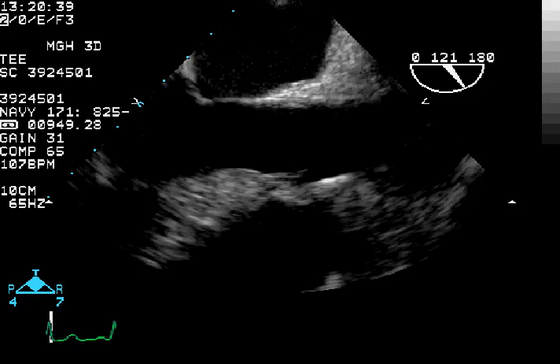

10、经食管超声图像伪像

虽然上面介绍的主要集中在常规经胸超声心动图,但上述伪像也经常在经食管超声心动图中遇到。图10显示了经食管超声心动图中一些常见的伪像。在这方面最相关的临床情况是(1)排除LAA中的血栓(图10E和10F)和(2)排除主动脉夹层(图10G和10H)。

图10经食管图像伪影。

(A)二尖瓣小叶的混响伪影,距离探头正好两倍,表现为左心室腔内的导线(视频15)。

(B)机械主动脉瓣在右心室(RV)(星号)的大部分上投射声学阴影,并在侧面(箭头)投射混响(彗星尾)(视频16)。

(C)房间隔穿刺的导管,由于在(中空)导管上下侧的反射,出现一系列紧密间隔的混响(箭头),并且由于在探头本身的反射,在距离探头两倍的距离处出现一个混响。

(D)疑似两个平行的主动脉(Ao)的镜像伪影(星号)。注意血流也产生镜像伪像(视频17)。

(E)左心耳疑似血栓的混响伪影。从多个角度(见图F)进行分析证实存在华法林嵴的混响(星号),而不是真正的血栓(视频18-19)。

(G)在升主动脉(视频20)中延伸的钙化窦管连接(箭头)的旁瓣伪影(箭头)不应被误解为夹层。

(H)同样,升主动脉中的回声可能会被误解为夹层。